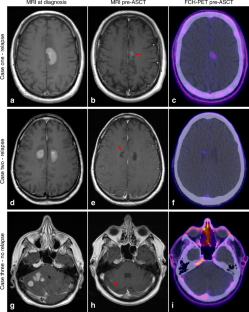

Millard, T., Sammour, F., Anthias, C. et al. Can pre-transplant 18F-choline positron emission tomography predict relapse following autologous stem cell transplantation in primary central nervous system lymphoma?. Bone Marrow Transplant 57, 113–115 (2022). https://doi.org/10.1038/s41409-021-01484-7

Kowa JY, Millard T, Goldman A, Sharma RK, Attygalle A, Mahalingham P et al. Are treatment response assessment maps (TRAMs) and 18F-choline positron emission tomography the future of central nervous system lymphoma imaging?. Br J Haematol. 2021. https://doi.org/10.1111/bjh.17632.